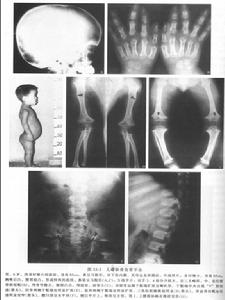

軟骨發育不全患兒軀幹長度相對正常,而手臂和腿較短。上臂和大腿比前臂和小腿更短。通常,頭顱較大、前額突出和塌鼻樑也是其特徵。有時,大頭顱是腦積水的表現,往往需要手術治療。還有手短,手指粗短,中指和無名指之間分離(三叉手)等特徵。軟骨發育不全是一種常染色體顯性遺傳病,通過軟骨內分化缺陷影響長骨的發育,病人表現出特徵性的短肢性體儒,外科手術是目前有效的治療方法,基因治療是未來的發展方向。

軟骨發育不全(二)頭顱增大有的病人有輕度腦積水,穹隆及前額突出,馬鞍型鼻樑,扁平鼻、厚嘴唇舌伸出(在嬰兒)。

(三)胸椎後突,腰椎前突,以後者為明顯。骶骨較水平使臀部特徵性的突出。

(四)胸腔扁而小,肋骨異常的短。

(五)手指粗而短,分開,常可見4、5指為一組,2、3指為一組,拇指為一組,似“三叉戟”。有的病人的伸肘動作輕度受限。

(六)下肢呈弓形,走路有滾動步態(rolling)。

X線表現①顱蓋大,前額突出,頂骨及枕骨亦較隆突,但顱底短小,枕大孔變小而呈漏斗型,其直徑可能只有正常人的1/2。如伴發腦積水側腦室擴張。②長骨變短,骨幹厚,髓腔變小,骨骺可呈碎裂或不齊整。在膝關節部位,常見骨端呈“V”形分開,而骨骺的骨化中心正好嵌入這V形切跡之中。由於骨化中心靠近骨幹,使關節間隙有增寬的感覺。下肢弓形,腓骨長於脛骨,上肢尺骨長於橈骨。③椎體厚度減少,但脊柱全長的減少要比四肢長度的減少相對少很多。自第一腰椎至第五腰椎,椎弓間距離逐漸變小。脊髓造影可見椎管狹小,有多處椎間盤後突。④骨盆狹窄,骼骨扁而圓,各個徑均小,髖臼向後移,接近坐骨切跡,有髖內翻,髖臼與股骨頭大小不對稱。肋骨短,胸骨寬而厚。肩胛角不銳利,肩胛盂淺而小。

①顱蓋大,前額突出,頂骨及枕骨亦較隆突,但顱底短小,枕大孔變小而呈漏斗型,其直徑可能只有正常人的1/2。如伴發腦積水側腦室擴張。

②長骨變短,骨幹厚,髓腔變小,骨骺可呈碎裂或不齊整。在膝關節部位,常見骨端呈“V”形分開,而骨骺的骨化中心正好嵌入這V形切跡之中。由於骨化中心靠近骨幹,使關節間隙有增寬的感覺。下肢弓形,腓骨長於脛骨,上肢尺骨長於橈骨。

③椎體厚度減少,但脊柱全長的減少要比四肢長度的減少相對少很多。自第一腰椎至第五腰椎,椎弓間距離逐漸變小。脊髓造影可見椎管狹小,有多處椎間盤後突。

④骨盆狹窄,骼骨扁而圓,各個徑均小,髖臼向後移,接近坐骨切跡,有髖內翻,髖臼與股骨頭大小不對稱。肋骨短,胸骨寬而厚。肩胛角不銳利,肩胛盂淺而小。